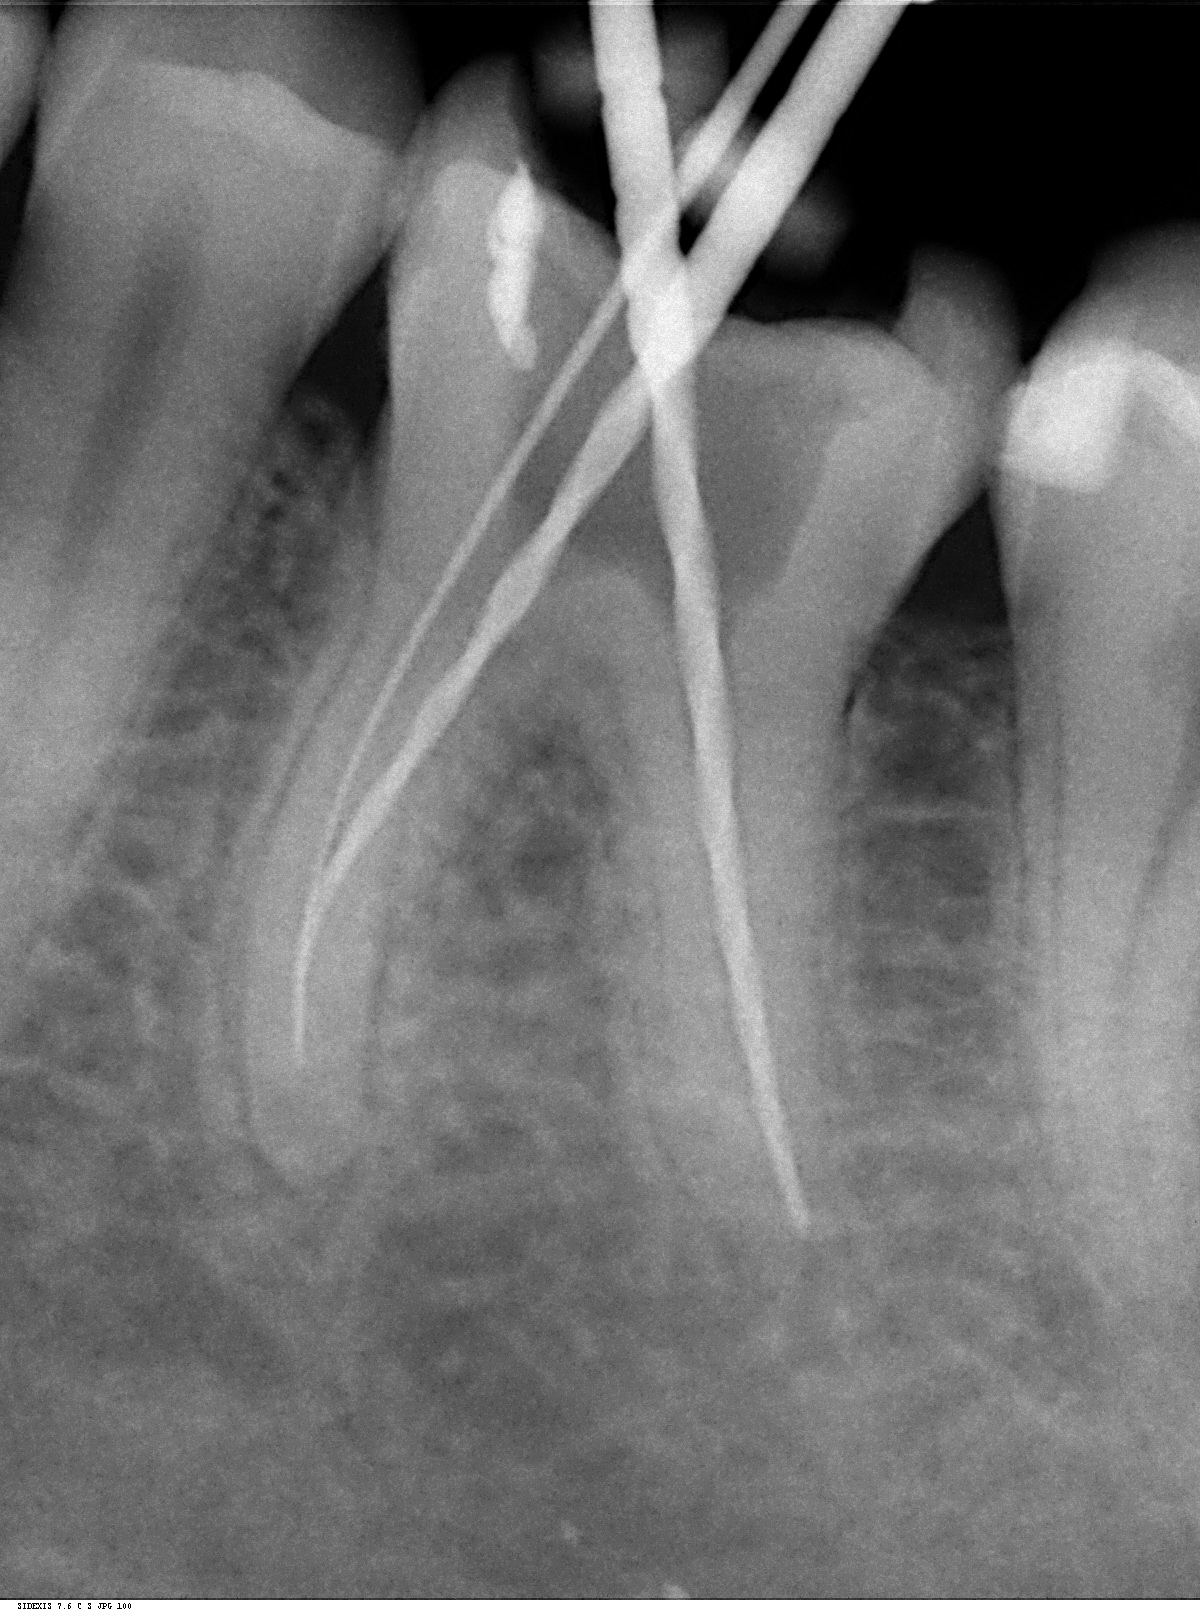

In der Behandlungsfolge wird der Wurzelkanal eröffnet, erweitert, gereinigt und abschließend mit einer Wurzelfüllpaste bakteriendicht verschlossen.

Im Rahmen der modernen Endodontie kommen in unserer Praxis besondere Maßnahmen wie die elektronische Wurzelvermessung und die maschinelle Wurzelkanalaufbereitung mit speziellen Feilen zum Einsatz.